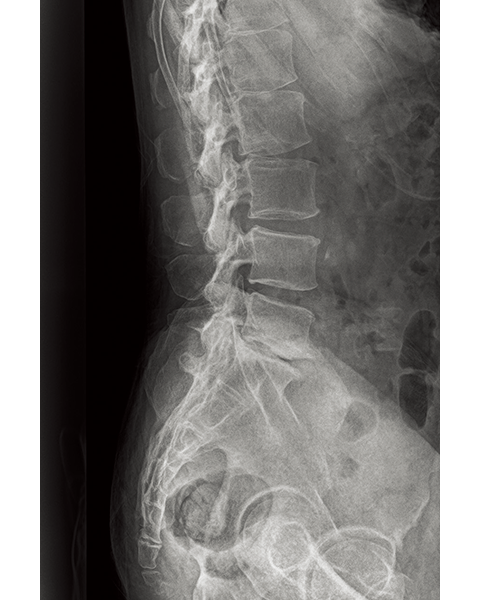

Lumber Spine

Comparison of Dynamic Visualization II vs. conventional processing images (Lumbar Spine)